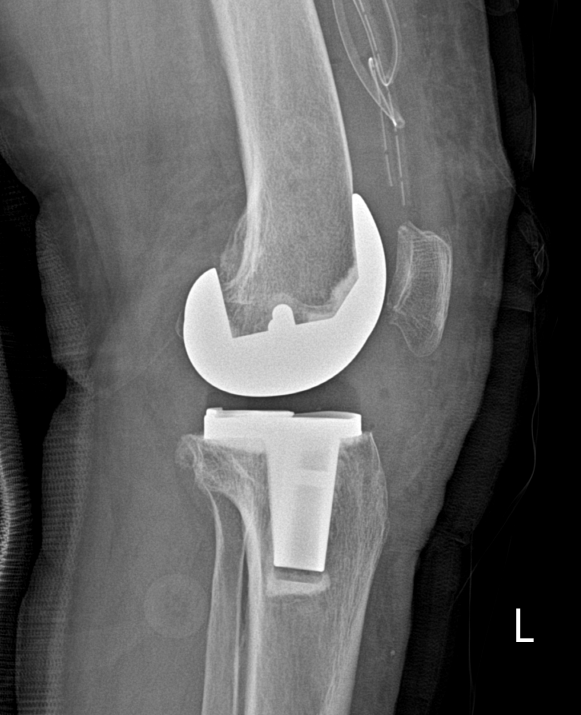

- 관절고정술, 절골술, 슬관절 전치환 성형술 등을 시행합니다.

- 무릎 안쪽의 Joint space가 좁게 나타난 것을 확인할 수 있습니다. 퇴행성 관절염이 진행되고 있는 모습입니다.

슬관절 전치환술의 목적

- 골 관절염(OA) 및 류마티스 관절염(RA) 환자의 통증감소

- 수술 후 일정수준 이상의 관절운동범위의 획득

- 해부학적 정렬 획득

- 슬관절에 가해지는 비정상적 모멘트를 제거하여 측부 인대의 대칭적인 긴장을 유발

- 굴곡구축과 함께 동반된 슬관절의 내반, 외반 변형 개선